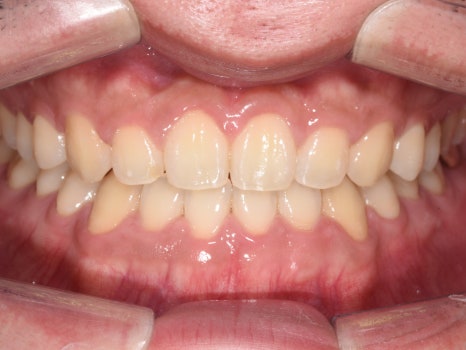

치료결과

실제 소요 기간 : 14개월

반대교합과 불규칙한 치아배열,

아래턱 돌출 등의 문제사항이

확연히 개선된 것을 알 수 있습니다.

예상 교정기간이 24개월이었으나

빠른 치아의 이동으로

10개월 단축된 14개월만에

빠르게 교정을 완료하였답니다.

아랫입술이 뒤로 들어가고,

반대교합이었던 앞니가

정상교합으로 자리잡은 것을

확인할 수 있습니다 :)